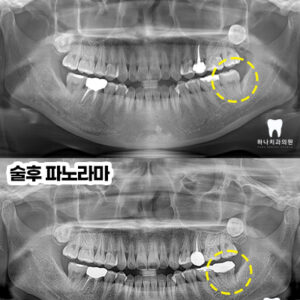

신정동치과 전체 치아 파절로 인한 전악 보철

신정동치과 전체 치아 파절로 인한 전악 보철   안녕하세요! 하나치과입니다~:) ​ 치아는 충치, 파절, 마모, 신경치료 이후 약화 등 여러 요인으로 쉽게 손상될 수 있는데요. ​ 손상이 심한 경우라면 단순한 수복재로는 원래 기능을 유지하기 어렵고 재손상 위험도 높아질 수 있어 치아 전체를 덮어 보호하는 크라운 치료가 필요할 수 있습니다. ​ 더보기…